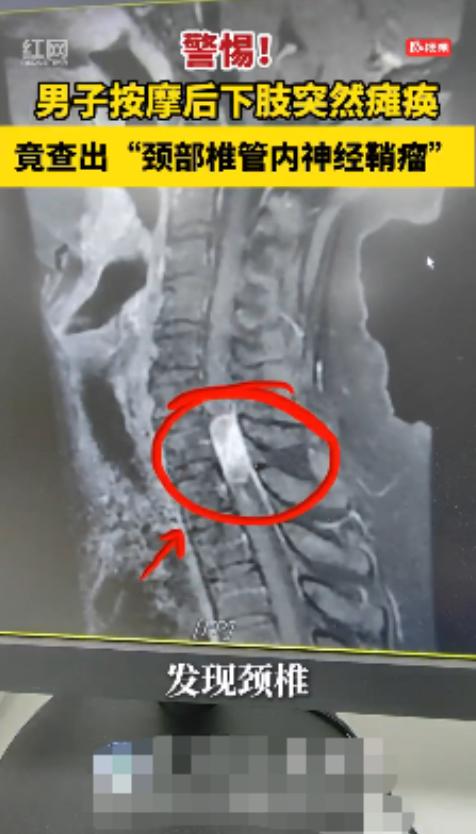

“悲剧还是发生了!”这句话最近在湖南宁乡的朋友圈里传得沸沸扬扬。 一名30多岁的男子,本想着去放松放松,结果一次普通的按摩,竟让他从一个大步流星的壮年人,变成了下肢瘫痪的病人。 信息来源:《男子按摩后下肢突然瘫痪 医生提醒:颈椎不好别胡乱按摩,严重可危及生命》红网 有时候,悲剧并不是突如其来的,而是你一念之间做出的“放松决定”。 湖南宁乡的一个男子,本想去按摩店舒缓一下颈椎疼痛,结果这一趟“放松之旅”,险些让他终身瘫痪。 这名男子三十出头,是个典型的办公室打工人。每天对着电脑十几个小时,肩颈酸胀已经成了家常便饭。 平时他也不太在意,想着“就是颈椎病,按一按就好了”。 最近那段时间,他的脖子越来越紧,低头就酸、抬头就痛,甚至晚上睡觉一翻身都“咯噔”作响。 他心想:“不能再拖了,得去放松放松。” 于是,在朋友的推荐下,他找了一家口碑还不错的按摩店。门口的广告牌上写着:“专业颈椎调理,舒筋活络,立竿见影。” 他看着挺正规,就进去了。 店里灯光柔和,空气中飘着一股淡淡的药油味。技师是个四十多岁的男人,笑得特别热情。 “兄弟,你这颈椎一看就不行啊,估计压着神经了。我这手法专治这个,包你按完轻松。” 男子听得挺舒服,没多想,就趴在按摩床上。 技师先是用力推拿,再来几下旋转动作。只听到“咔——”的一声脆响,男子只觉得脖子一麻,一股电流顺着脊柱往下窜,腿一下子发麻。 “师傅,我腿有点麻。” “正常,说明通经络了。” 技师边说边继续用力按。 男子心里虽然有点慌,但想着人家是“专业的”,于是忍着不适硬是按完了全程。 等他起身时,腿软得厉害,脚底发虚,差点摔倒。 技师笑着说:“回家休息一下就好,明天准舒服!” 男子半信半疑地走了出去,谁也没想到,这一句“明天就好”,成了噩梦的开始。 第二天一早,男子起床准备上厕所。 他一蹲下去,顺利得很,可当他要站起来时,却发现腿不听使唤。 他试着撑着洗手台站起来,腿一点力气都没有。慌乱中,他叫来了妻子:“我……我站不起来了。” 妻子以为他开玩笑,但看到他脸色惨白、满头冷汗,顿时慌了。两人赶紧打车去了医院。 医生连忙安排检查,问了几个关键问题: “你昨天有没有摔倒?” “有没有按摩或推拿?” 男子点点头,说自己昨天按了颈椎。 医生脸色立刻变了:“赶紧做核磁!” 几个小时后,真相终于揭开—— 男子颈椎椎管内长了一个肿瘤! 而那次按摩,正好“按”在肿瘤上,造成神经受压,直接导致下肢瘫痪。 医生当场告知家属:“再拖一会儿,可能就永久瘫痪了。” 那一夜,手术室的灯一直亮到凌晨。医生小心翼翼地为他切除肿瘤,整整七个小时,家属守在外面一刻也不敢合眼。 凌晨三点,医生推门出来:“手术成功,肿瘤切除了。” 家人当场流泪——他们知道,这一刀,挽回的不只是腿,更是整个家庭的希望。 术后前几天,男子仍然下肢无力。护士轻声问他:“能感觉到脚吗?” 他拼命集中精神,终于,脚趾微微动了动。 那一刻,他哭了——那不是疼,而是活着的实感。 经过几个月的康复,他终于能再次下地行走。虽然脚步还不稳,但他每走一步,心里都在感谢医生,也在后悔那天的冲动。 医生后来告诉他: “你这是幸运。肿瘤压迫脊髓神经的患者,一旦受到刺激,很可能终身瘫痪。” 其实,很多人都和他一样,哪里痛就想去按摩。 但有些疼痛不是“筋络不通”,而是身体在发出警告。 对此大家有什么想说的?欢迎在评论区留言讨论!